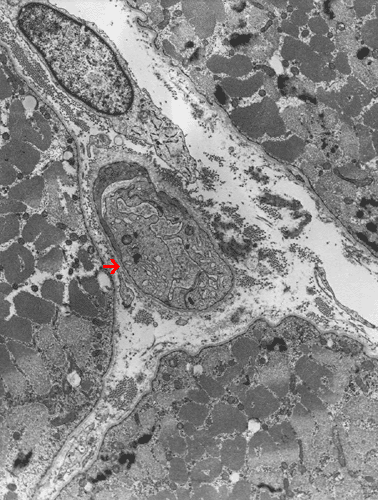

Note the endothelial cells (Ú) have enlarged cytoplasm.